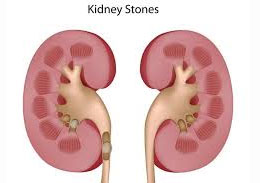

A kidney stones is a solid pieces of the material which is made in the kidney from the mineral in urine, it's also called a renal calculus or nephrolith. The kidney stone leave the body in the urine and small pieces of the stone may pass with the urine. If size of the stones are growing and size has abnormal then stones can blockage of the ureter. The stone leads to pain in the stomach and lower back. The symptoms of the stones are: fever, vomiting, nausea, painful urine and blood in the urine.

The renal colic is a kind of pain, the main reason of this pain is kidney stone. The kidney stone is crystals that form from chemicals in the urine. Generally the stone develops when a single chemical is present too much in the urine. The stones may block the flow of the urine and it can produce the pain if urine travels down the tube of the urinary system. In the symptoms of the renal colic involve pain in the abdomen, pain in the back side, blood flow in the urine, fever, vomiting, abnormally urine colour, etc.